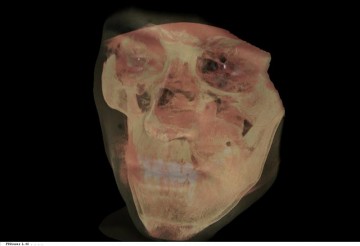

«Imagina despertar de una operación sin poder hablar, con una sonda por la nariz porque no puedes comer por la boca, sin poder masticar y con parte de tu mandíbula extirpada porque te han extraído un tumor», explicó Wikfaardt en una entrevista con Efe.

Aún hoy, si un paciente es diagnosticado con un tumor en la mandíbula, durante un periodo de entre 2 y 5 años tiene que pasar en distintas ocasiones por la mesa de un cirujano que extrae un trozo de su peroné y lo talla, para ocupar el espacio que ha dejado la extracción del tumor.

Aplicando máquinas del mundo industrial a la medicina, se pueden generar los distintos implantes de manera precisa y hacer simulaciones de lo que será la operación para que el cirujano sólo tenga que preocuparse de colocarlos bien.

Cuando los tumores son benignos, un molde de titanio con la forma del implante se inserta en la pierna del paciente para que su peroné adquiera la forma correcta del implante.

Después de llevarlo unos 3 meses en la pierna, el paciente vuelve al quirófano para que le extraigan el tumor y le inserten el trozo de hueso con la forma precisa.

En el caso de que se halle un carcinoma, el tumor ha de extirparse en menos de seis semanas, con lo cuál se omite la fase de adaptación de la prótesis al peroné pero se mantiene la precisión exacta gracias a la impresión digital del molde.

«El paciente despierta con boca, dientes, pudiendo hablar y listo para recibir sus sesiones de quimioterapia y radioterapia», aclaró Wolfaardt.